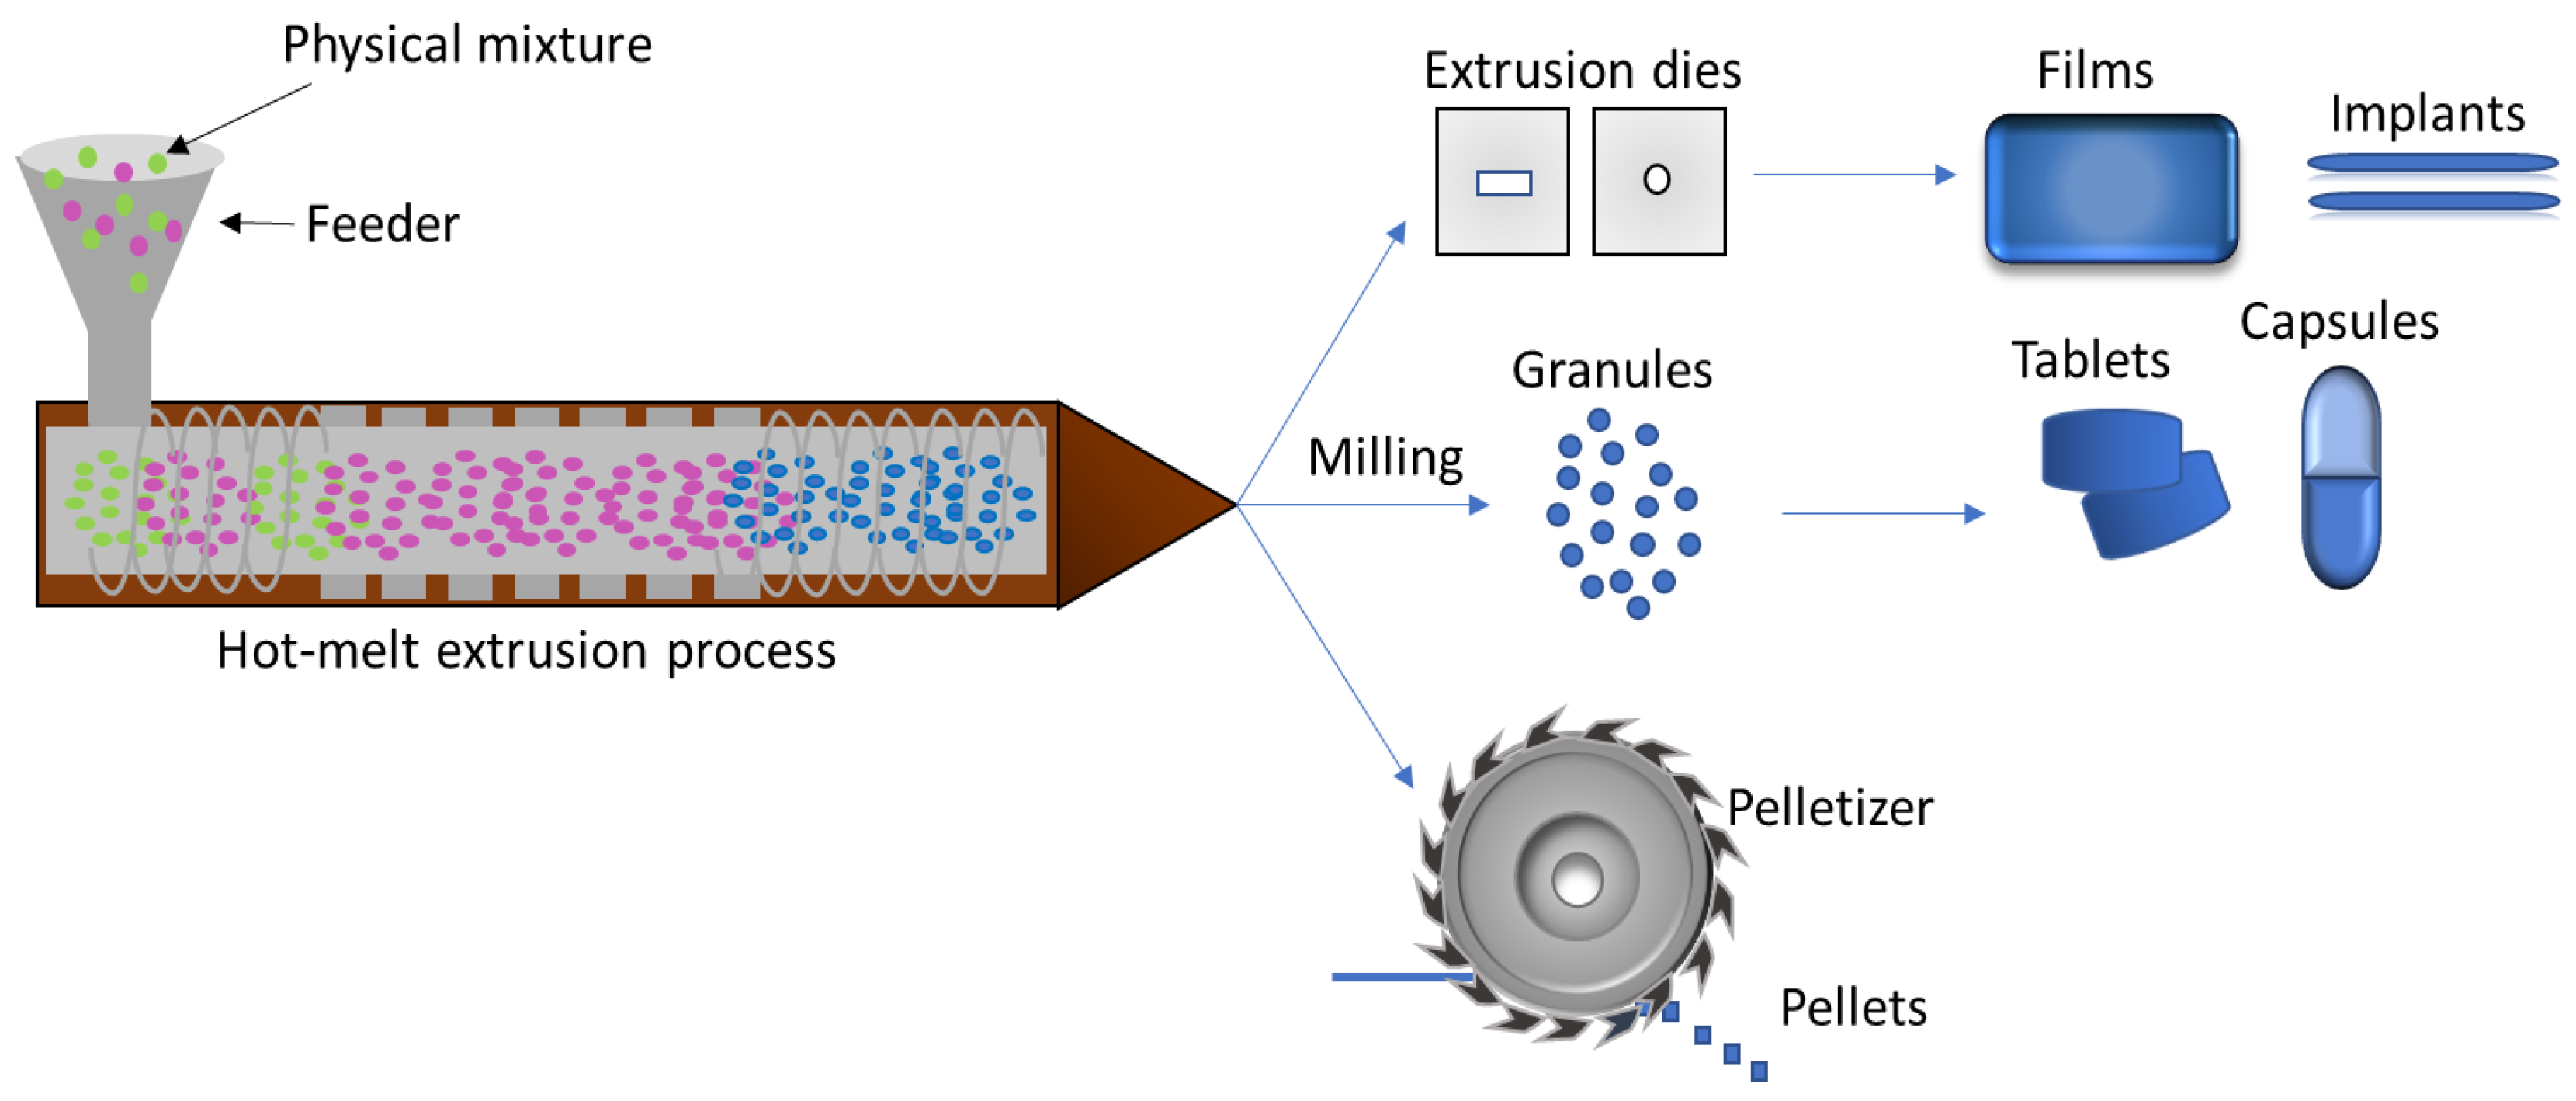

5.3. Hot Melt Extrusion

- Wilson, M.; A Williams, M.; Jones, D.S.; Andrews, G.P. Hot-melt extrusion technology and pharmaceutical application. Ther. Deliv. 2012, 3, 787–797. [Google Scholar] [CrossRef]

- Patil, H.; Tiwari, R.V.; Repka, M.A. Hot-Melt Extrusion: From Theory to Application in Pharmaceutical Formulation. AAPS PharmSciTech 2016, 17, 20–42. [Google Scholar] [CrossRef] [PubMed]

- Censi, R.; Gigliobianco, M.R.; Casadidio, C.; Di Martino, P. Hot Melt Extrusion: Highlighting Physicochemical Factors to Be Investigated While Designing and Optimizing a Hot Melt Extrusion Process. Pharmaceutics 2018, 10, 89. [Google Scholar] [CrossRef] [PubMed]

- Madan, S.; Madan, S. Hot melt extrusion and its pharmaceutical applications. Asian J. Pharm. 2012, 7, 123–133. [Google Scholar]

- Tambe, S.; Jain, D.; Agarwal, Y.; Amin, P. Hot-melt extrusion: Highlighting recent advances in pharmaceutical applications. J. Drug Deliv. Sci. Technol. 2021, 63, 102452. [Google Scholar] [CrossRef]